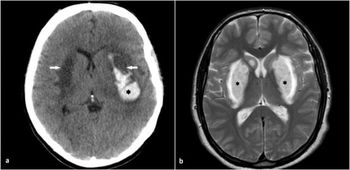

Iranian researchers diagnosed ischemic stroke in COVID-19-positive child with no other symptoms.

CT and MRI scans show neurological impacts.

Case of acute necrotizing encephalopathy could be first of many.